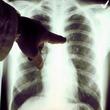

Kanserli olup olmadığınızı 5 dakika içinde anlayan teknoloji test sürecini tamamladı. Kanser ile savaşta son derece önemli olan bu teknoloji bakalım hastalığı nasıl yakalıyor? Bu Linki Görmeniz İçin SupersatForuma Uye Olmanız Gerekmektedir.